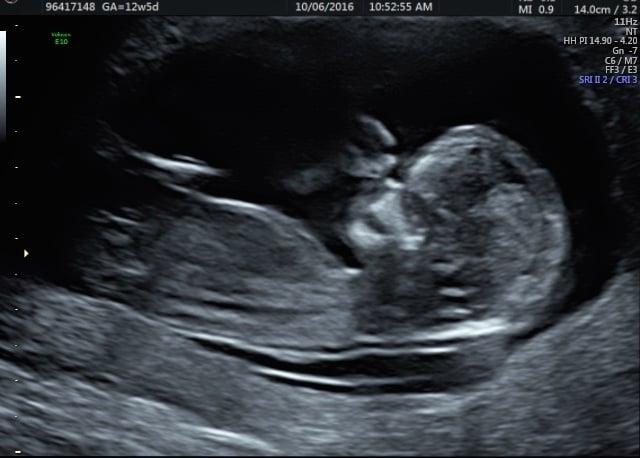

We had the NT scan done today, along with the blood work. 12w5d. All the indicators look good. Our baby looks healthy as can be so far. Very wiggly. It took awhile for the tech to get the measurements because he/she was to busy flipping around. As the wand was on him he literally did a complete flip at one point. It was pretty incredible. Also scheduled our 20 week scan yesterday. November 29th is a VERY long ways away.